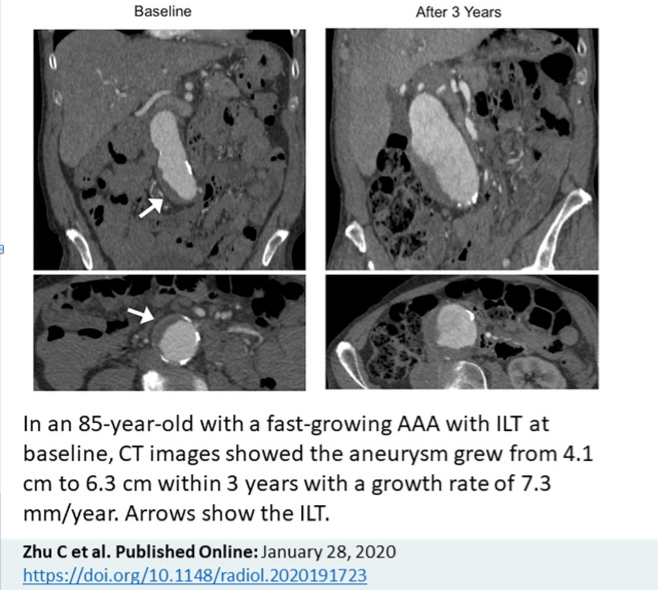

Abdominal Aortic Aneurysms Aaa Cardiovascular Disorders Merck Manuals Professional Edition